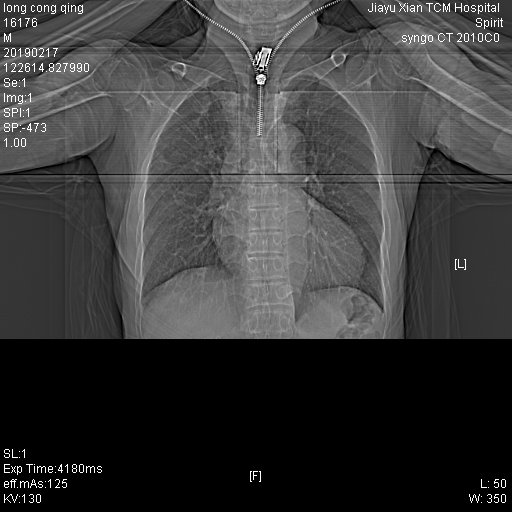

CT53511:男,60Y,胸部

咳嗽,请老师看下

右肺上叶可见斑片状及索条状影,余部见数个毛玻璃结节影及云絮状影,密度均匀,边缘欠清晰。

考虑:1、右肺上叶尖后段继发性肺结核。2、毛玻璃结节影及云絮状影,建议抗炎治疗后复查。

右上下肺及左肺舌叶下舌段可见多发斑片索条影,右肺尤著,大部分病灶边缘模糊,部分病灶位于胸膜下。考虑:两肺感染性病变,右肺尤著。建议治疗后复查。右上肺少许陈旧性结核。